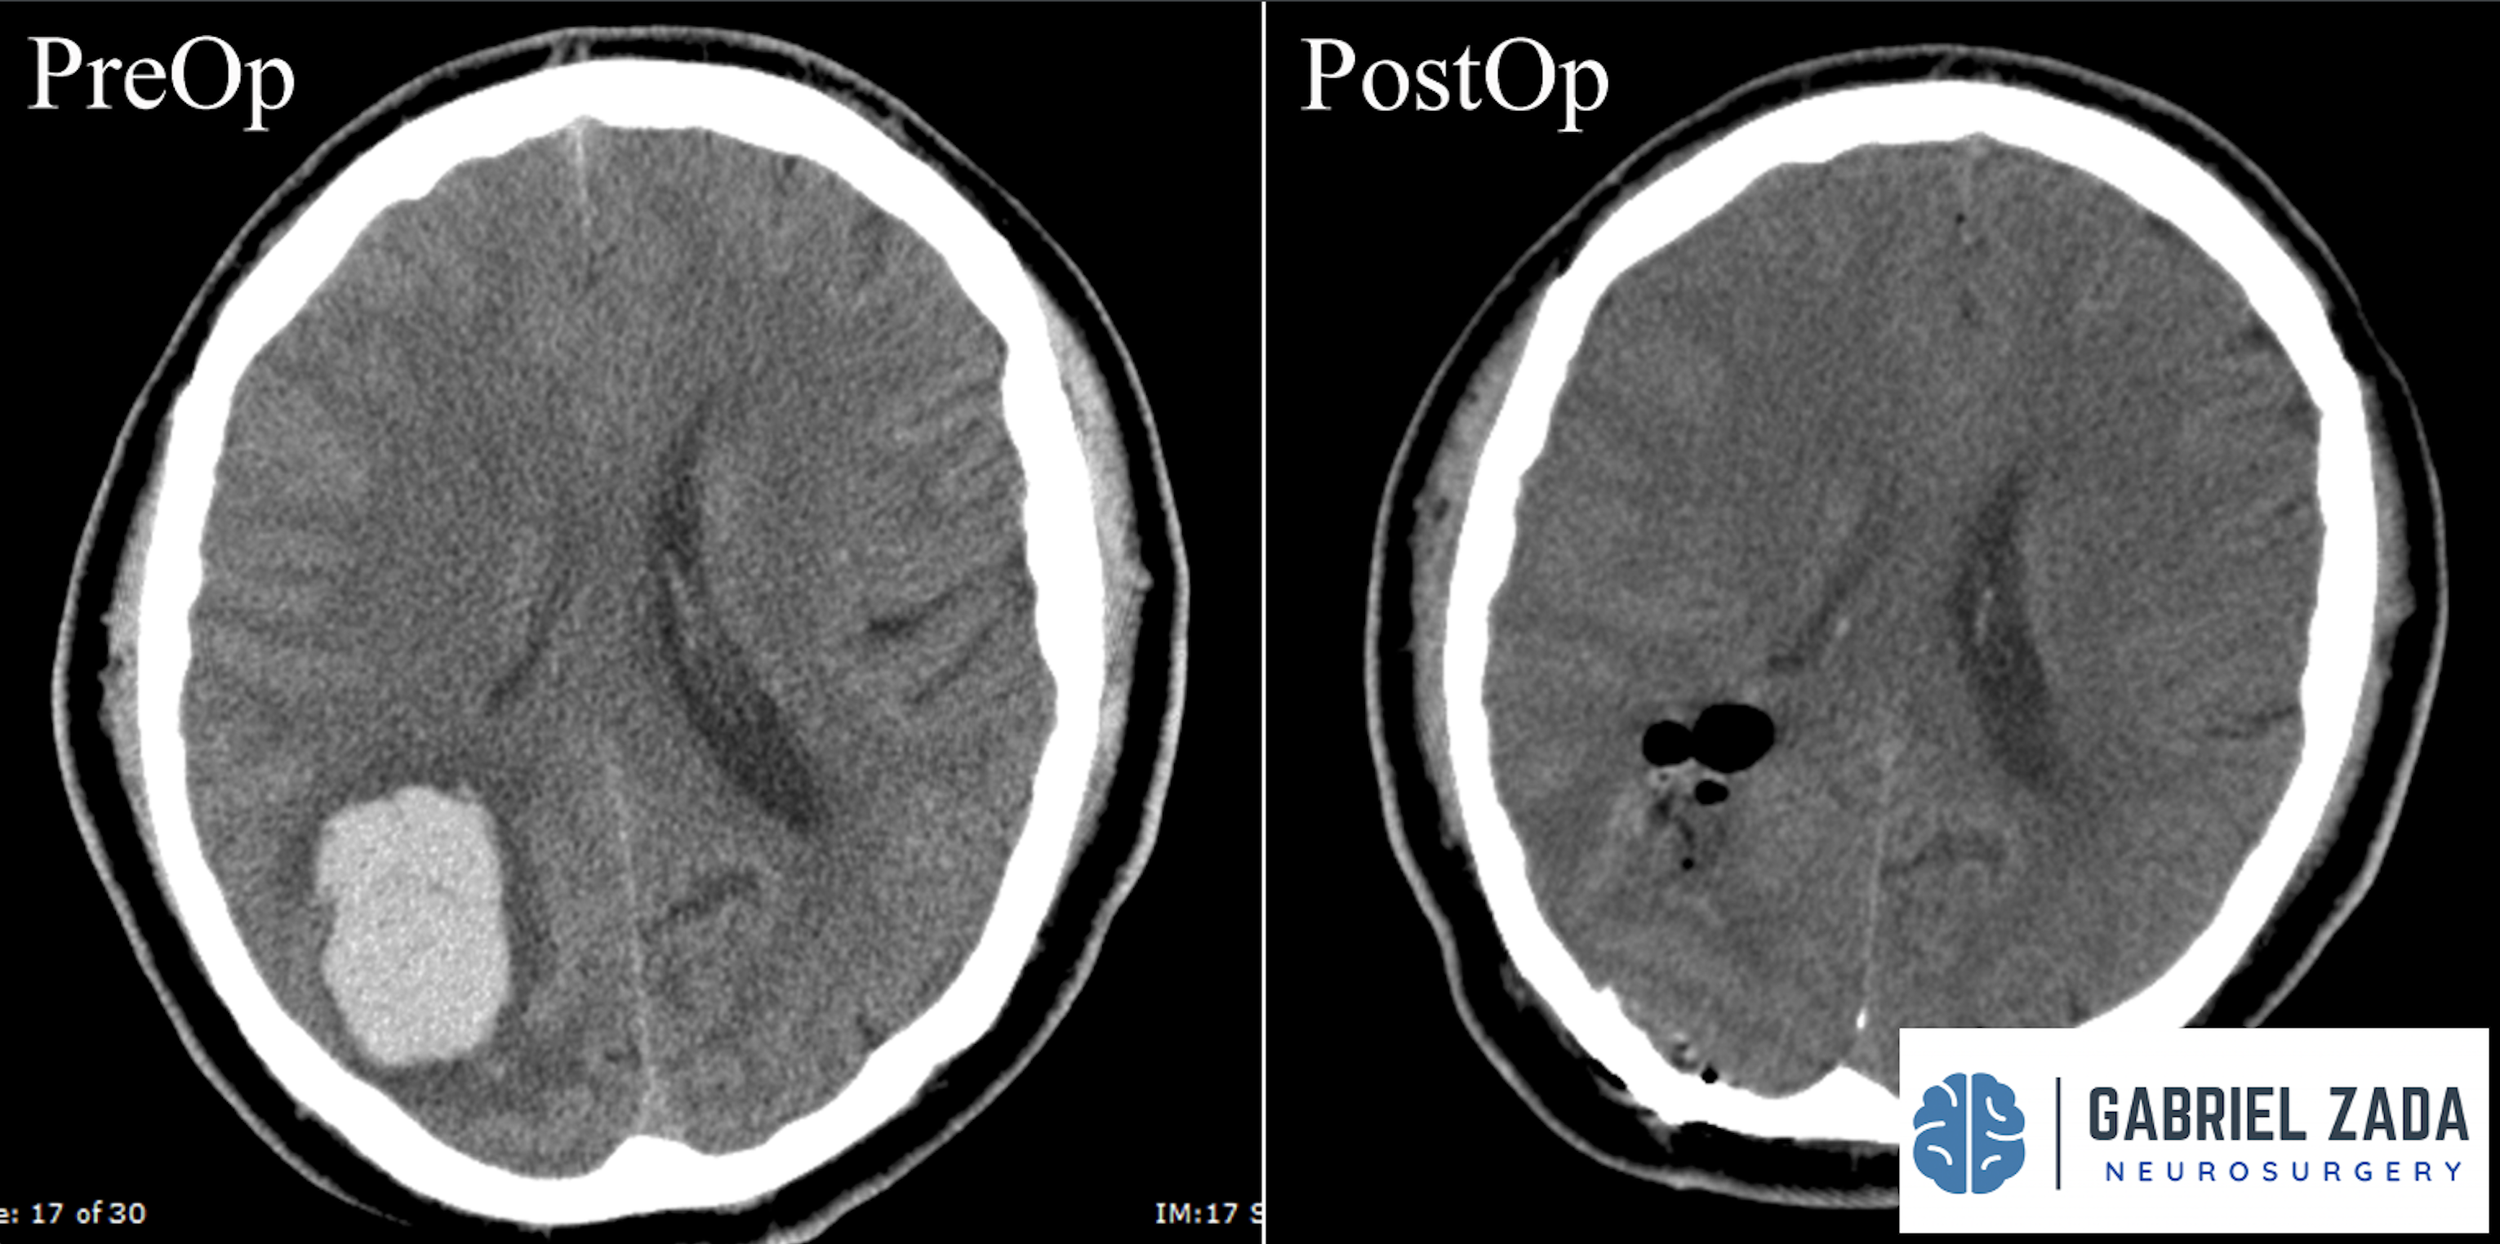

Explore this comprehensive gallery featuring pre‑ and post‑operative imaging of patients with skull‑base tumors treated by Gabriel Zada, MD, MS, FAANS, FACS. These cases highlight Dr. Zada’s expertise in advanced neurosurgical techniques and outcomes.

*Representative cases shown for educational purposes. All images de-identified. Individual results vary.